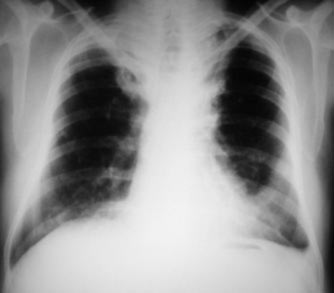

Radiología del tórax

Rx. tórax PA: Observamos el clásico tórax en tonel de un paciente enfisematoso, amplio en su base, espacios intercostales muy amplios, diafragma plano, aumento del volumen y de la trasparencia pulmonar a predominio de vértices pulmonares, en los que observamos bandas fibroticas radiopacas a predominio del lobulo superior derecho, botón aortico prominente y una silueta cardiaca elongada con reforzamiento de los hileos vasculares pulmonares.

Radiología del tórax Pos operatoria

Rx. Tórax PA y L-izq. un mes posterior a la intervención, el paciente refiere sentirse mejor, camina y hace esfuersos leves a moderados aunque persisten dolores torácicos atribuibles a la intervención quirúrgica, aparte de los signos radiológicos antes mencionados característicos del tórax enfisematoso. Se observa radiopacidad difusa en vértice superior derecho y borramiento del seno costo-diafragmático izquierdo, suturas de alambre en esternón, mejor apreciadas en la rx. lateral, en forma cruzada  (x), detalle a señalar debido a reintervención para osteosíntesis esternal, por fuga de los alambres con cabalgamiento esternal en su post operatorio inmediato.